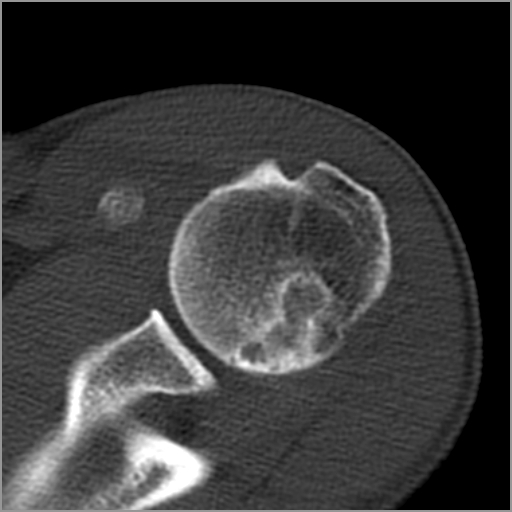

以下是引用zxd95在2008-7-19 18:45:00的发言:[br]囊性病灶边缘硬化、皮质变薄但连续——提示生长时间长、良性病变——考虑左肱骨头骨囊肿。[br]

以下是引用杀毒软件在2008-7-19 18:55:00的发言:[br]考虑:骨巨细胞瘤可能性大